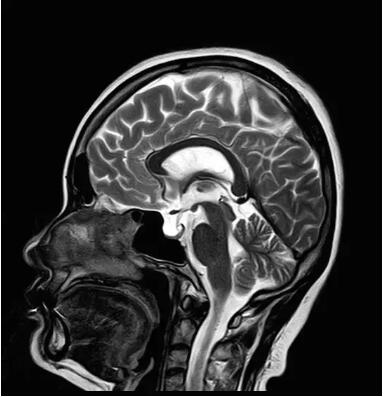

見所未見 微小腫瘤無處遁藏——

“螢火蟲”成像技術(shù) 顱內(nèi)腫瘤微小病灶檢出新發(fā)現(xiàn)

此技術(shù)主要用于神經(jīng)系統(tǒng)惡性腫瘤,以及其他腫瘤腦轉(zhuǎn)移瘤篩查。傳統(tǒng)情況下做腫瘤腦轉(zhuǎn)移篩查,很容易漏掉5mm以下小病灶,臨床發(fā)現(xiàn)后干預(yù)治療比較晚,要實現(xiàn)2mm高空間分辨率和超薄層全腦掃描在保證信噪比的情況下需要很長時間大概十多分鐘,而且薄層增強(qiáng)序列顱內(nèi)血管呈高亮信號,會干擾顱內(nèi)小病灶的觀察,血管和小病灶區(qū)分困難。佳能”螢火蟲”成像技術(shù)既可以實現(xiàn)高空間分辨率和超薄層(最薄可實現(xiàn)0.2mm)全腦掃描,掃描時間短,2-3分鐘即可實現(xiàn)全腦3D掃描,同時避免了血管高亮信號的干擾,對顱內(nèi)原發(fā)或繼發(fā)的微小腫瘤檢查有重大意義。“螢火蟲”成像技術(shù)具有磁敏感效應(yīng),對于亞急性血敏感敏感,可以區(qū)分出血和強(qiáng)化的腫瘤。